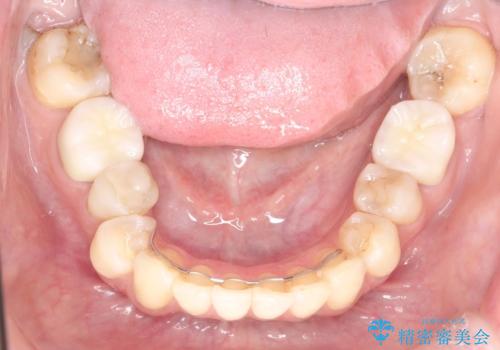

穴があいたクラウンのやり直しは根管治療から

- 穴のあいてしまった被せものは除去し仮歯へ

→根管治療をやり直し、土台を立て直す

→新たにクラウンを製作する

根管治療からのやり直しは時間と労力がかかりますが、基礎の部分をしっかりと仕上げることで、安心して長く使っていただく事ができると考えています。

被せものの種類:Bellezza